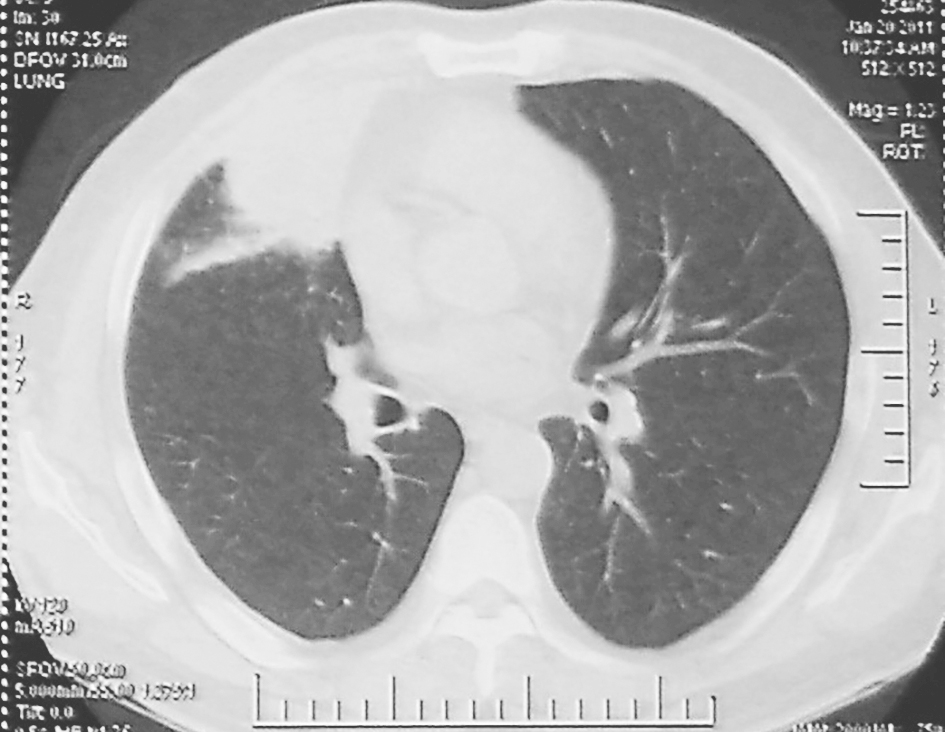

图2 胸部CT表现(2011-01-20)

胸部CT可见右肺中叶实变影较前缩小